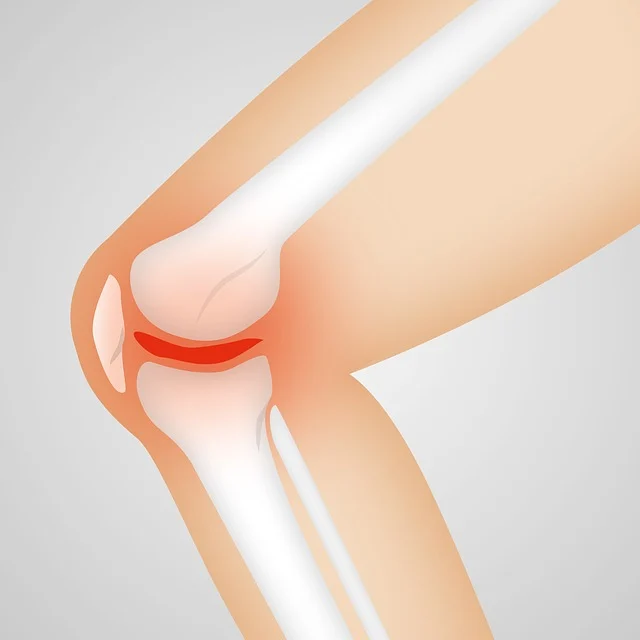

콘드로이친(Chondroitin)은 주로 관절과 연골의 건강을 지원하는 데 사용되는 자연 발생 물질입니다. 콘드로이친은 연골의 주요 구성 요소 중 하나로, 연골의 수분 보유 능력과 탄력을 유지하는 데 중요한 역할을 합니다. 콘드로이친은 보통 콘드로이친 황산염 형태로 보충제에서 찾아볼 수 있으며, 종종 글루코사민과 결합하여 관절 보조제로 사용됩니다.

연골은 관절을 보호하는 부드러운 조직으로, 관절의 원활한 움직임을 돕고 충격을 흡수합니다. 연령 증가, 부상, 또는 특정 건강 상태로 인해 연골이 손상되거나 마모될 수 있으며, 콘드로이친은 이러한 연골의 손상을 늦추거나 관절 건강을 개선하는 데 도움을 줄 수 있습니다.

- 수분 보유 증진: 콘드로이친은 연골 내 수분 보유 능력을 증가시켜 연골이 부드럽고 유연하게 유지되도록 돕습니다. 이는 관절의 움직임을 원활하게 하고 마모를 줄이는 데 중요합니다.

- 연골 보호: 콘드로이친은 연골 세포를 자극하여 핵심 연골 구성 요소인 콜라겐과 프로테오글리칸의 합성을 촉진합니다. 또한, 연골을 분해하는 효소의 활동을 억제하여 연골 손상을 늦출 수 있습니다.

- 염증 감소: 콘드로이친은 염증을 유발하는 화학 물질의 생산을 감소시키는 항염증 효과를 가지고 있습니다. 이는 관절염과 같은 염증성 관절 질환에서 통증과 부기를 완화하는 데 도움이 됩니다.